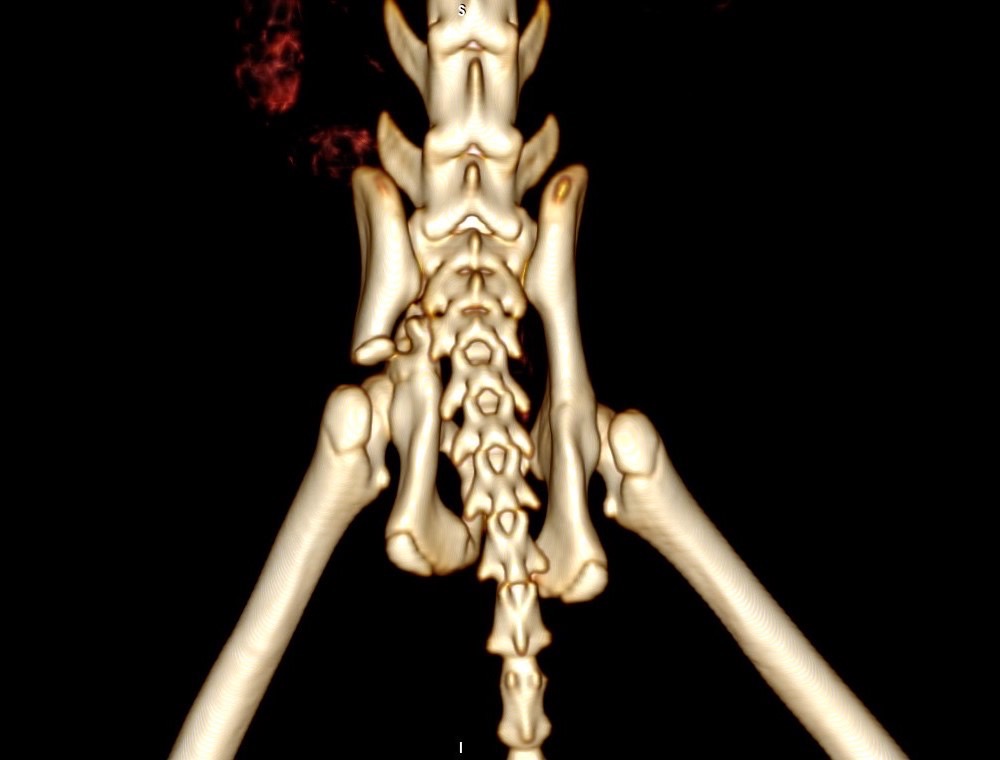

狗狗 車禍 骨盆骨折

狗狗的骨盆骨折相對於常見的四肢骨折 不容易單純靠xray 診斷及擬定手術計畫藉由電腦斷層影像的支援 能提高手術成功的機率

14kg 11歲的莓莓 術後10個月追蹤 行動自如一切正常喔

術前

術後

電腦斷層影像